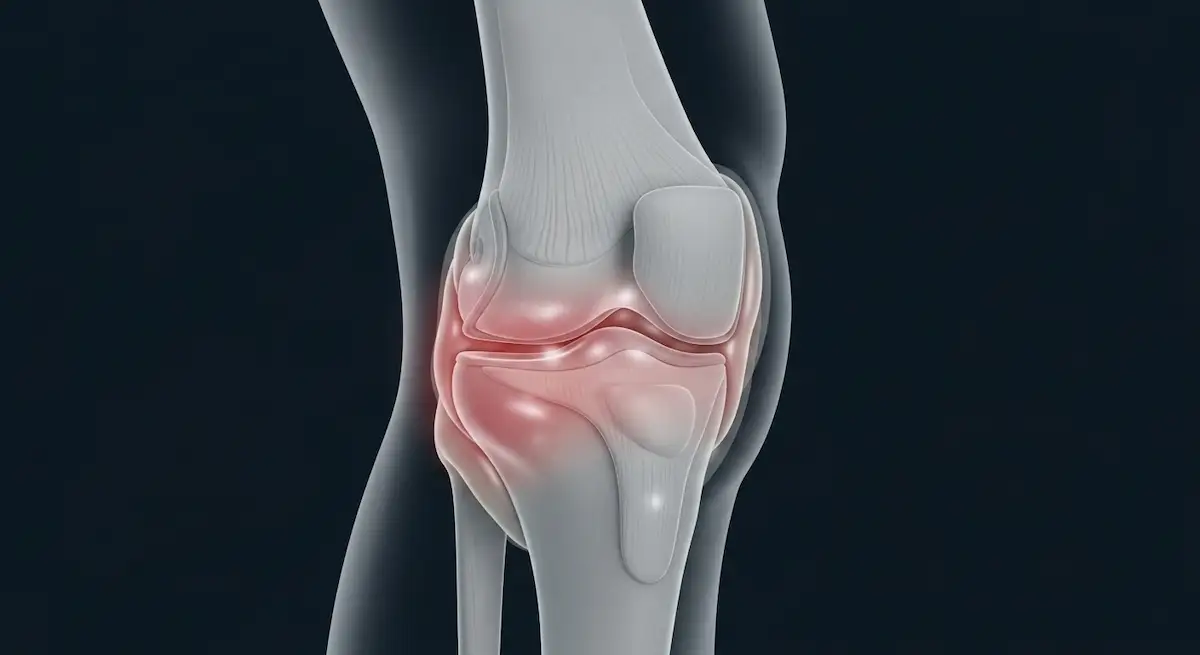

A gordura infrapatelar (conhecida como gordura de Hoffa) fica entre o tendão patelar e a porção anterior do fêmur e da tíbia.

Atua como amortecedor, reduzindo atrito dentro do joelho e ajudando a distribuir cargas.

Quando sofre microtraumas, impactos repetidos ou atritos por desalinhamentos, ocorre um processo inflamatório que chamamos de síndrome de Hoffa ou hoffite.